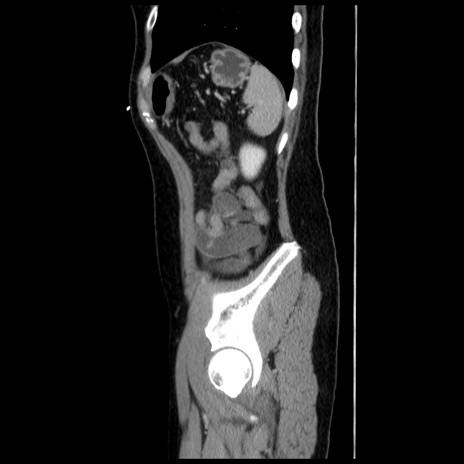

症例10(矢状断像)

【症例】 50歳代女性

【主訴】 腹痛

【現病歴】前日生レバーを食べた。今朝に排便あり。 昼前に突然発症の腹痛を生じ、当院救急外来を受診した。

【既往歴】 子宮筋腫にてで子宮全摘後

【身体所見】 意識清明、腹部:平坦、軟、下腹部やや左を中心に圧痛・反跳痛あり、筋性防御あり

【データ】WBC 7800、CRP 0.07